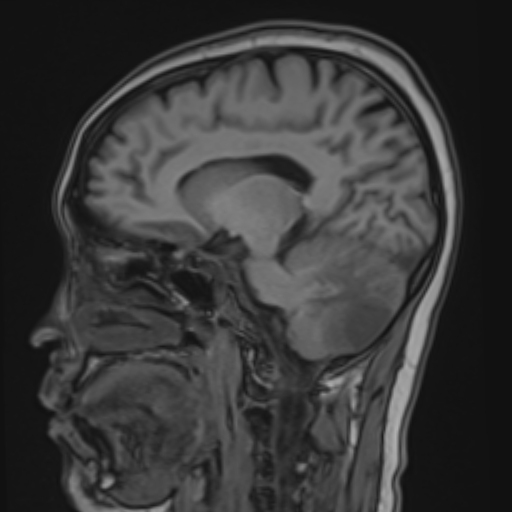

Enhanced myometrial vascularity is not a uterine AVM. This review clarifies definitions, key Doppler/MRI findings & management to avoid unnecessary embolization, hysterectomy & complications in post pregnancy bleeding. @StanfordBodyRad @stanfordRad bit.ly/463EX7M